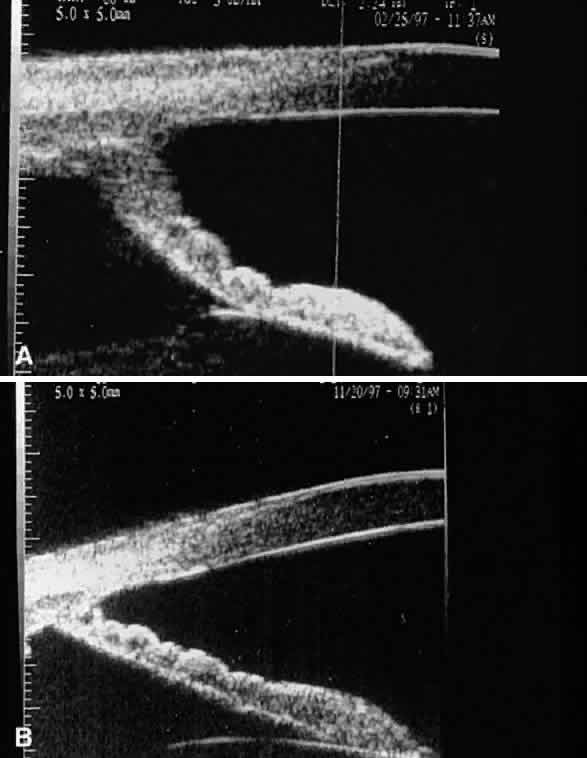

Accumulation of exfoliative material may be detected histopathologically throughout the anterior segment to include the lens, iris, trabecular structures, conjunctiva, ciliary body, and zonules. The deposition of fibrillar eosinophilic material on the anterior lens capsule is the classic histopathologic feature of XFS (Fig. 9). Ultrastructural studies also indicate some degree of actual exfoliative changes or peeling of the anterior lens capsule74 (Figs. 10 and 11). In addition, Ashton and associates describe a degenerative band containing exfoliative material within the inner half of the lens capsule.5 Bertelsen and coworkers independently noted projection of coarse fibrils from the lens surface into the deep portion of the lens capsule to form an amorphous layer of the lens capsule between the lens epithelium and normal lens capsule.6 Thus, studies indicate that exfoliative material accumulates on the anterior lens surface but also that the lens capsule itself may be involved, and that the underlying epithelial layer may at least partially contribute to the production of the exfoliative material.

Exfoliative material consists of an irregular meshwork of fibers composed of fibrillar subunits.74,92 Masses of these fibers correspond to the material seen clinically (see Fig. 10). The individual fibrils, which measure 6 to 8 nm in diameter and exhibit cross-banding at 10- to 12-nm intervals, are hypothesized to consist of macromolecules with a protein backbone and polysaccharide side chains.93–95 In contrast to collagen, the amino acid content of exfoliative material lacks hydroxyproline.96 Ringvold and Husby noted histochemical, immunologic, and ultrastructural features that led them to classify exfoliative material as an amyloid-like substance.97 Repo and associates note Congo red-positive staining for amyloid in the vessel walls of 7 of 13 iris specimens from exfoliation patients and believe that these findings support the theory that XFS is associated with amyloid.59 Immunohistochemical studies by other investigators show heparin sulfate and chondroitin sulfate proteoglycans, laminin, entactin/nidogen, fibronectin, and amyloid P protein to be components of exfoliation material.98,99 Schlötzer-Schrehardt and coworkers suggest that the material may be an expression of a disordered extracellular matrix synthesis.98